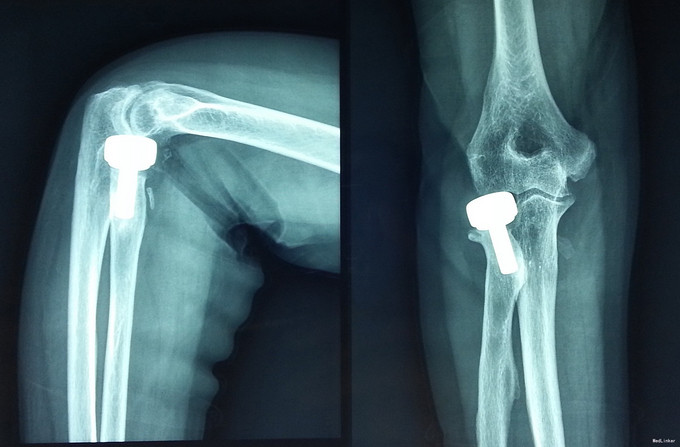

诊断为肘关节恐怖三联征(肘关节后脱位伴桡骨头和尺骨冠状突骨折),消肿后予以切开复位Wright桡骨小头假体置换,外侧副韧带修补,冠状突骨块小,未行固定。

术后近两年,桡骨近端假体承载处骨赘增生,但患者功能良好,无不适主诉,疗效满意